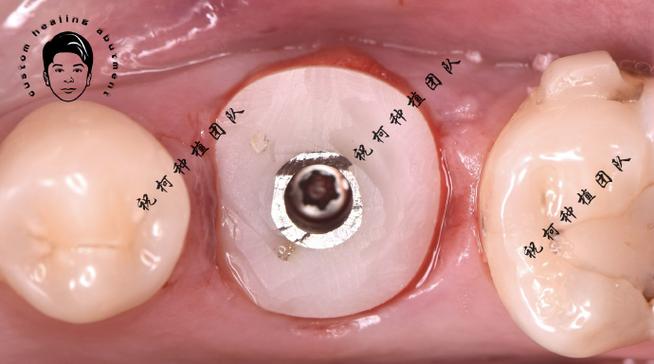

试戴:

- 患者复诊,医生取出愈合基台(如果还在)。

- 将制作好的个性化基台手动旋入种植体内部。

- 关键检查点:

- 完全就位: 基台应能无阻力、无晃动地完全就位到种植体平台,如果就位困难,可能需要调整基台内部结构或种植体连接处。

- 边缘密合: 基台边缘应与种植体平台紧密贴合,无可见缝隙,可通过牙周探针检查或使用显微镜观察。

- 无咬合干扰: 在正中及非正中咬合下,基台不应有早接触或干扰,可能需要调磨。

- 穿龈形态: 观察基台穿龈部分的形态是否与牙龈组织协调,牙龈袖口是否自然、健康。

- 固位与稳定: 基台应稳固,无松动。